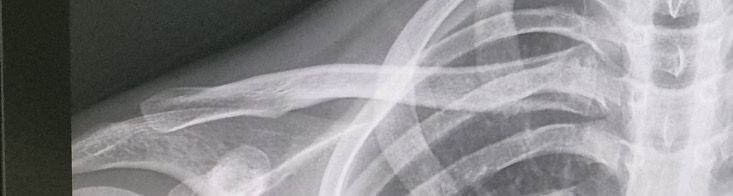

쇄골 골연령 나이가 만으로 몇세 정도인가요?

쇄골 성장판 나이가 만으로 몇세정도 인가요?

사진상으로는 연령대를 파악하는데 어려움이있습니다 일정기간을가지고 다시 촬영을하면서 비교해본다면 확인할수있겠지만 이 한사진으로만으로는 파악할수없습니다

하나의 사진상으로는 골 연령을 파악하기는 어려울 수 있고, 최소 몇개월 단위 간격으로 사진을 찍으시어 비교를 해야만 정확한 골연령의 추측이 가능합니다.

쇄골의 골연령은 일반적으로 25세 전후에 완전히 성장합니다 남성은 대개 20세에서 25세 사이에 성장판이 닫히고 여성은 조금 더 이른 18세에서 22세 사이에 닫힙니다. 개인차가 있을 수 있어 정확한 연령은 개인의 성장 상태에 따라 다를 수 있습니다!

단적인 엑스레이로는 골연령을 파악하기 어려울 수 있습니다. 최소 6개월에서 1년정도의 간격으로 경과를 비교를 하여야 정확한 골연령을 추측할 수 있습니다.

단순 엑스레이만으로는 확인하기가 쉽지 않습니다. 피검사나 골밀도 검사를 통해서 정확하게 확인 가능합니다. 엑스레이에서는 보통 뼈의 정렬이나 골절 여부 정도 확인 가능합니다. 자세한건 정형외과나 재활의학과 가셔서 확인해보시는게 정확한 답변을 얻을 수 있을것으로 보입니다. 성장판은 민감한 부분일 수 있기 때문에 제대로된 답변이 중요할거 같습니다 .